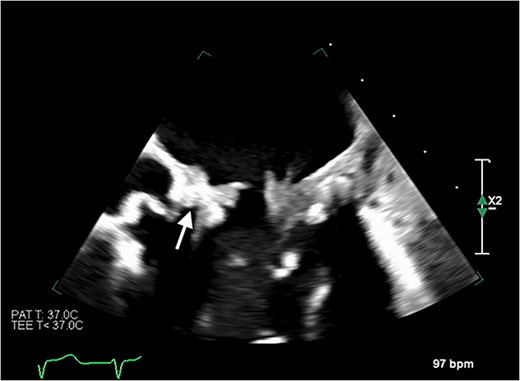

Echocardiography revealed a 1.2 cm pedunculated mass attached to the anterior mitral valve leaflet (AMVL) with severe mitral regurgitation (Fig. 1). Computed tomography imaging revealed multiple hepatic lesions (suspected septic emboli, Fig. 2), and a cavitating mass in the posterior aspect of the left upper lobe of the lung (Figs 3 and 4). Magnetic resonance imaging showed multiple cerebral lesions (Fig. 5), also thought to be septic emboli. Her presentation was suspected to be due to infective endocarditis rather than ischaemic, as troponin was negative, and coronary angiography was unremarkable. She was therefore treated promptly with intravenous vancomycin and gentamicin as per local antimicrobial guidelines. However, she failed to recover, and her case was reviewed in the regional in-house urgent cardiac surgical multidisciplinary team meeting. Considering her persistent fever, as well as the recurrent emboli, the decision was made to transfer her to our centre for emergency surgery.

Transoesophageal echocardiogram showing the pedunculated mass on the anterior mitral valve leaflet.